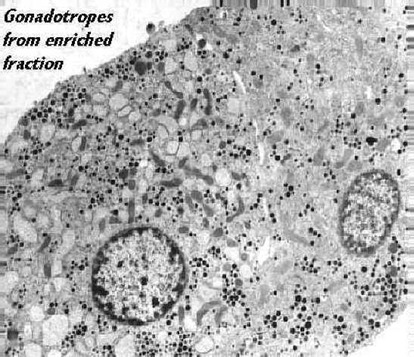

This electron micrograph shows a view of large gonadotropes from a fraction enriched in such cells. The cells are characterized by profiles of dilated rough endoplasmic reticulum and numerous secretory granules scattered throughout the cell cytoplasm. Sometimes the granules are of two sizes